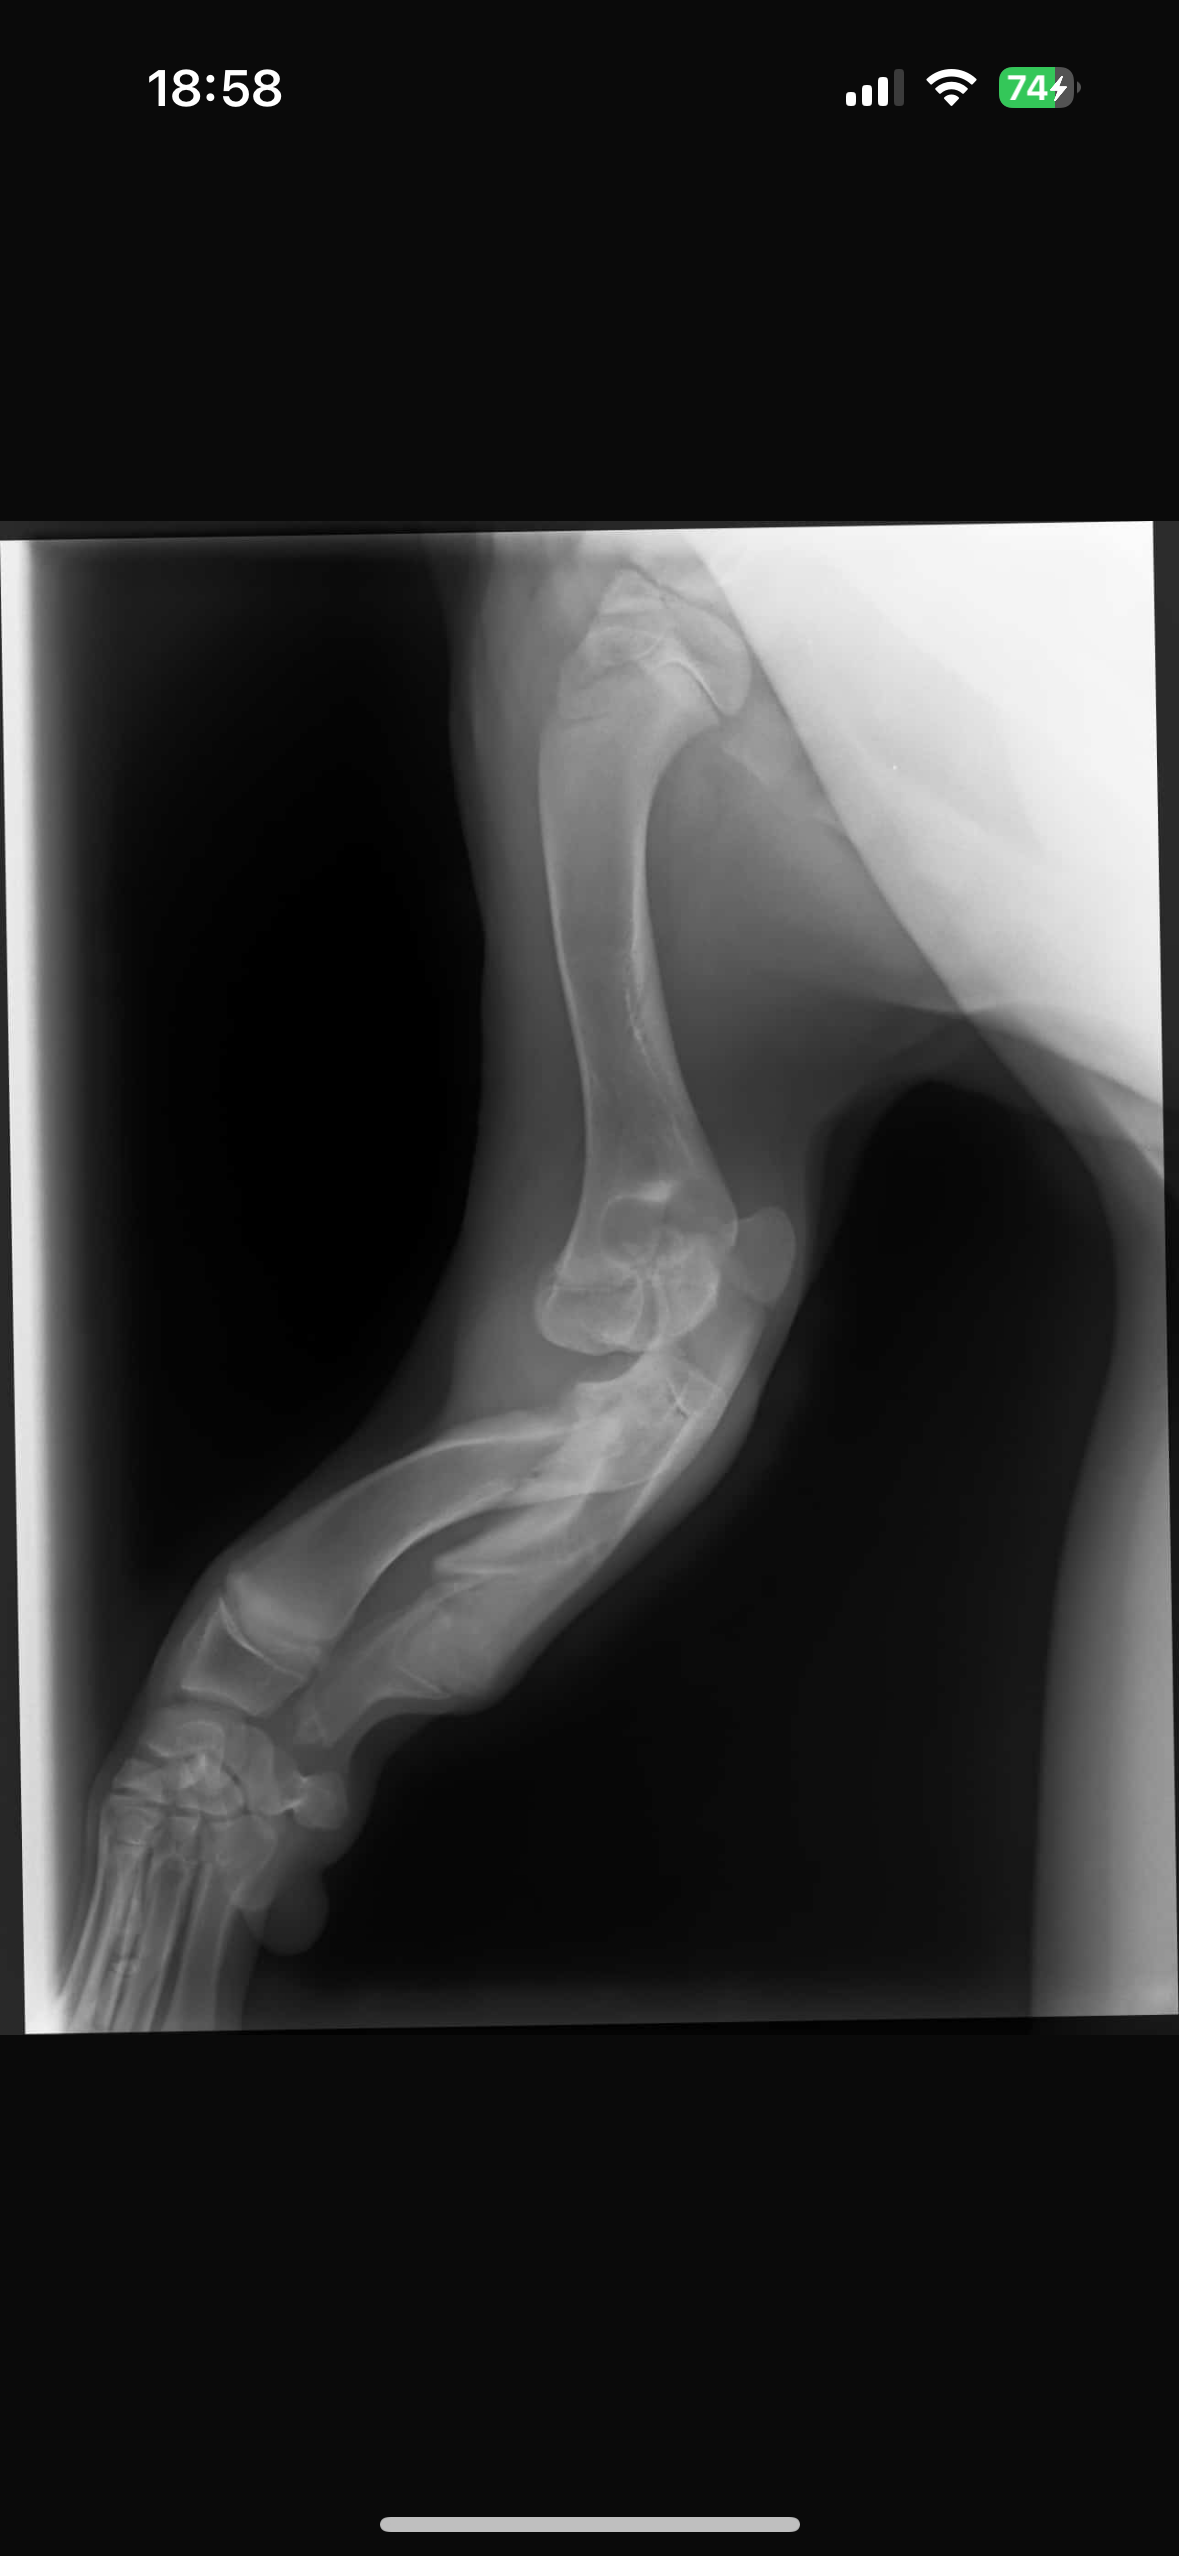

ABER leider wurde Mogli mit einer schweren Fehlbildung an beiden Vorderbeinen geboren. Jeder Schritt bedeutet für ihn Schmerz und ohne eine Operation wird Mogli niemals richtig laufen können.

Mit einer speziellen Operation besteht die Chance, dass Mogli endlich ein schmerzfreies, glückliches Leben führen.

Die Operation wird vom Spezialisten Dr. Tack durchgeführt.